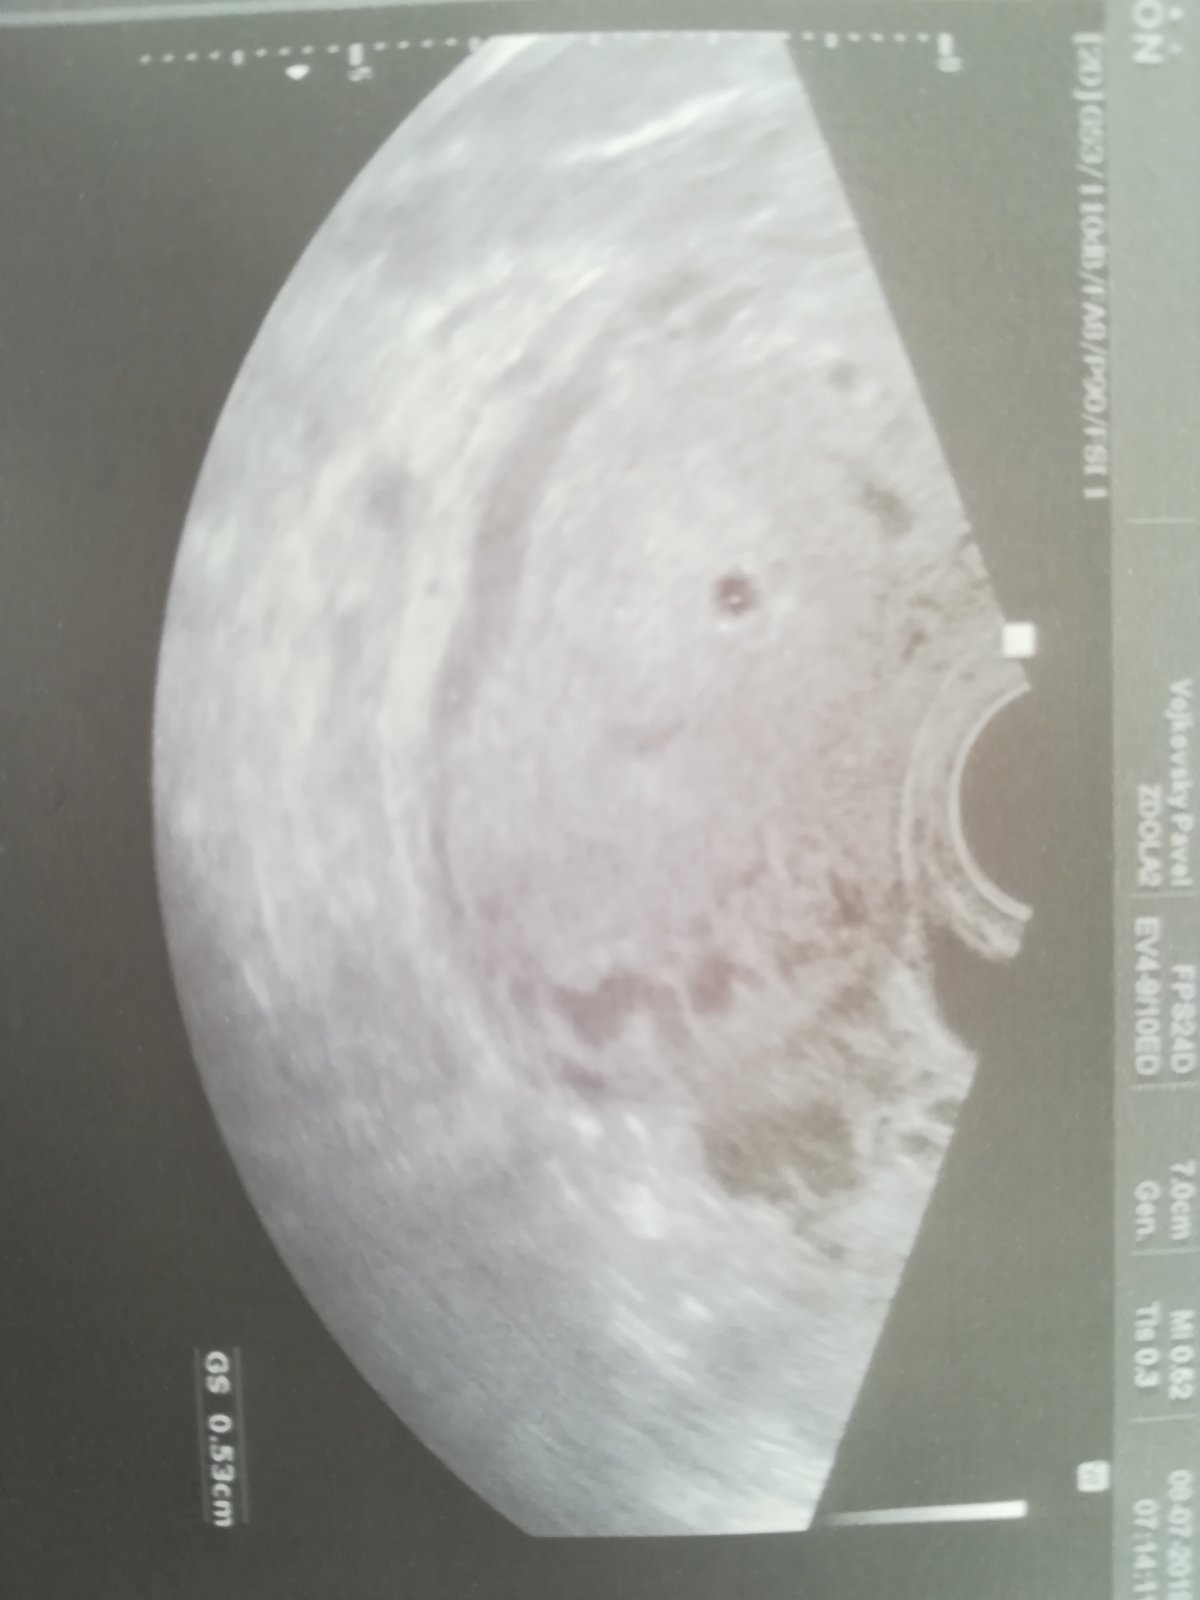

Holky mám takový dotaz. Cca 4 dny zpoždění. Na testech pořád duch 🤷♀️ nijak nesili tak nevím 🤷♀️ je možné, že i tak jsem když testy nesili? K dr chci jít až příští týden.